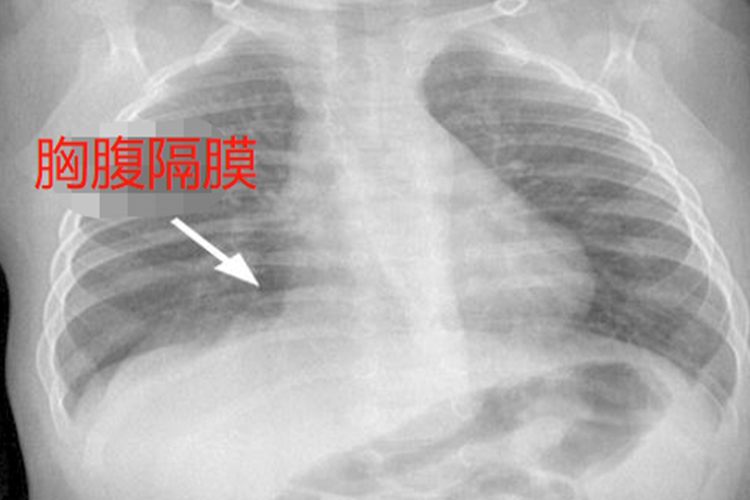

胸腔隔膜称为胸腹隔膜,位于人体体表肋弓下,在心脏和双侧肺脏下面,隔膜大概的位置在剑突下,胸后面平行第六胸椎部位,将胸腔和腹腔分隔开。